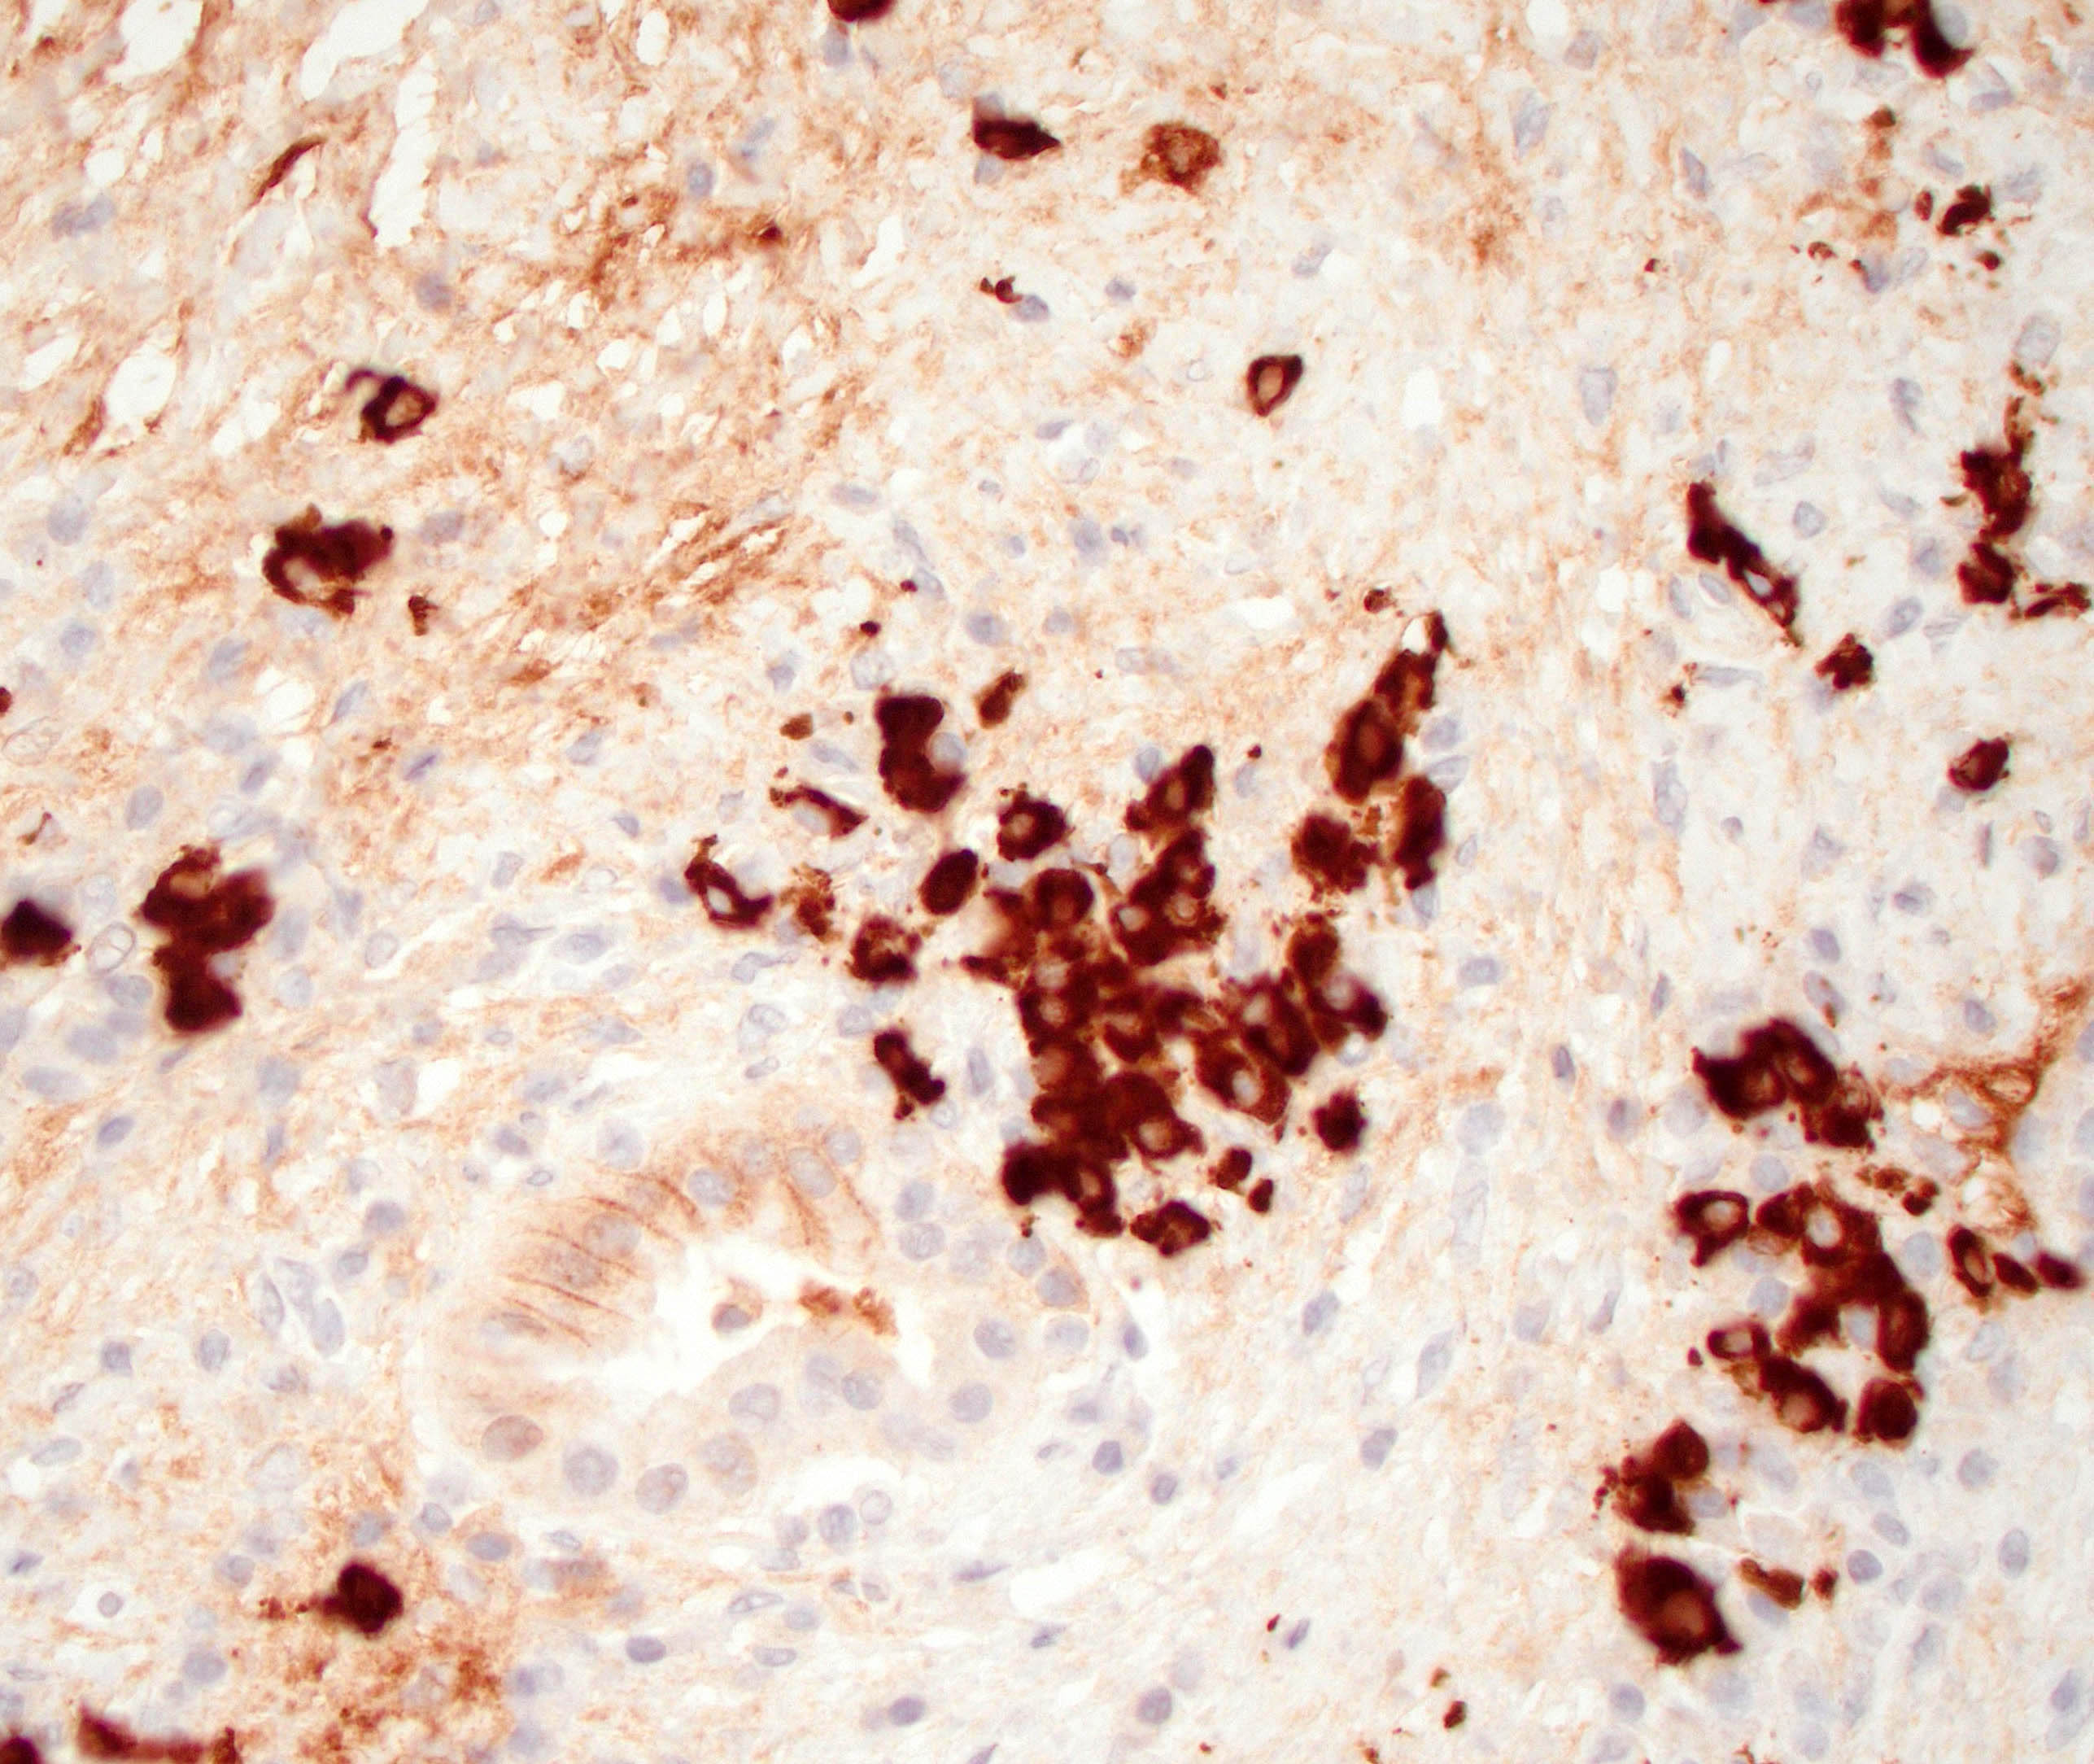

Positive stains

- IgG and IgG4

- > 10 IgG4 positive cells per high power field in biopsy specimens (Pancreas 2011;40:352)

- > 50 IgG4 positive cells per high power field in resection specimens (Virchows Arch 2018;472:545)

- IgG4/IgG ratio > 40% (Virchows Arch 2018;472:545)

- Elastic: highlights remnant veins in longstanding autoimmune pancreatitis

- Masson trichrome: highlights storiform fibrosis

- Comment: H&E sections demonstrate pancreatic parenchyma with dense storiform fibrosis and numerous chronic inflammatory cells including abundant plasma cells. A partially obliterated vein is seen. Immunohistochemical stain for IgG4 shows increased IgG4 positive plasma cells (up to 20 - 25 per high power field). The combined findings are most consistent with autoimmune pancreatitis type 1.